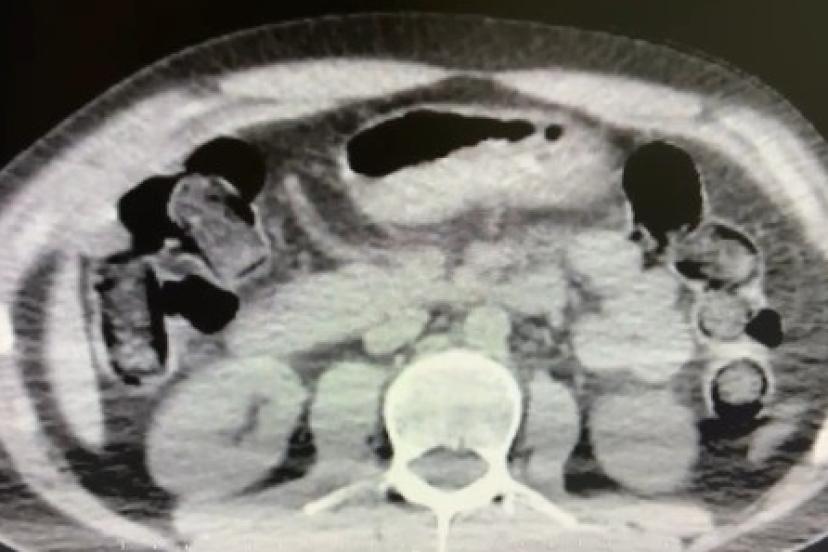

Nevşehir İl Emniyet Müdürlüğü Narkotik Suçlarla Mücadele Şube Müdürlüğü ekipleri, kentte uyuşturucu ve uyarıcı madde ticareti yapmak ve kullanmak suretiyle vatandaşları zehirleyen sokak satıcılarına yönelik çalışma başlattı. Cumhuriyet Başsavcılığı koordinesinde çalışmalarını yoğunlaştıran ekipler, şüpheliler S.B. ve O.R.’nin ’yutma yöntemi’ ile kente uyuşturucu madde sevk edeceği bilgisi üzerine operasyon düzenledi. Şüphelilerin ikametlerinde ve araçlarında yapılan aramada 101 kapsül halinde 722 gram uyuşturucu madde, 1 adet hassas terazi, uyuşturucu madde sevkiyatında yutma yönteminde kullanılan muhtelif materyaller, uyuşturucu madde ticaretinden elde edilen 20 bin 210 TL, bin 320 euro ve 10 ABD doları ele geçirildi. Emniyetteki işlemlerinin ardından adliyeye sevk edilen 2 şüpheli, çıkarıldıkları mahkemece tutuklanarak cezaevine gönderildi.